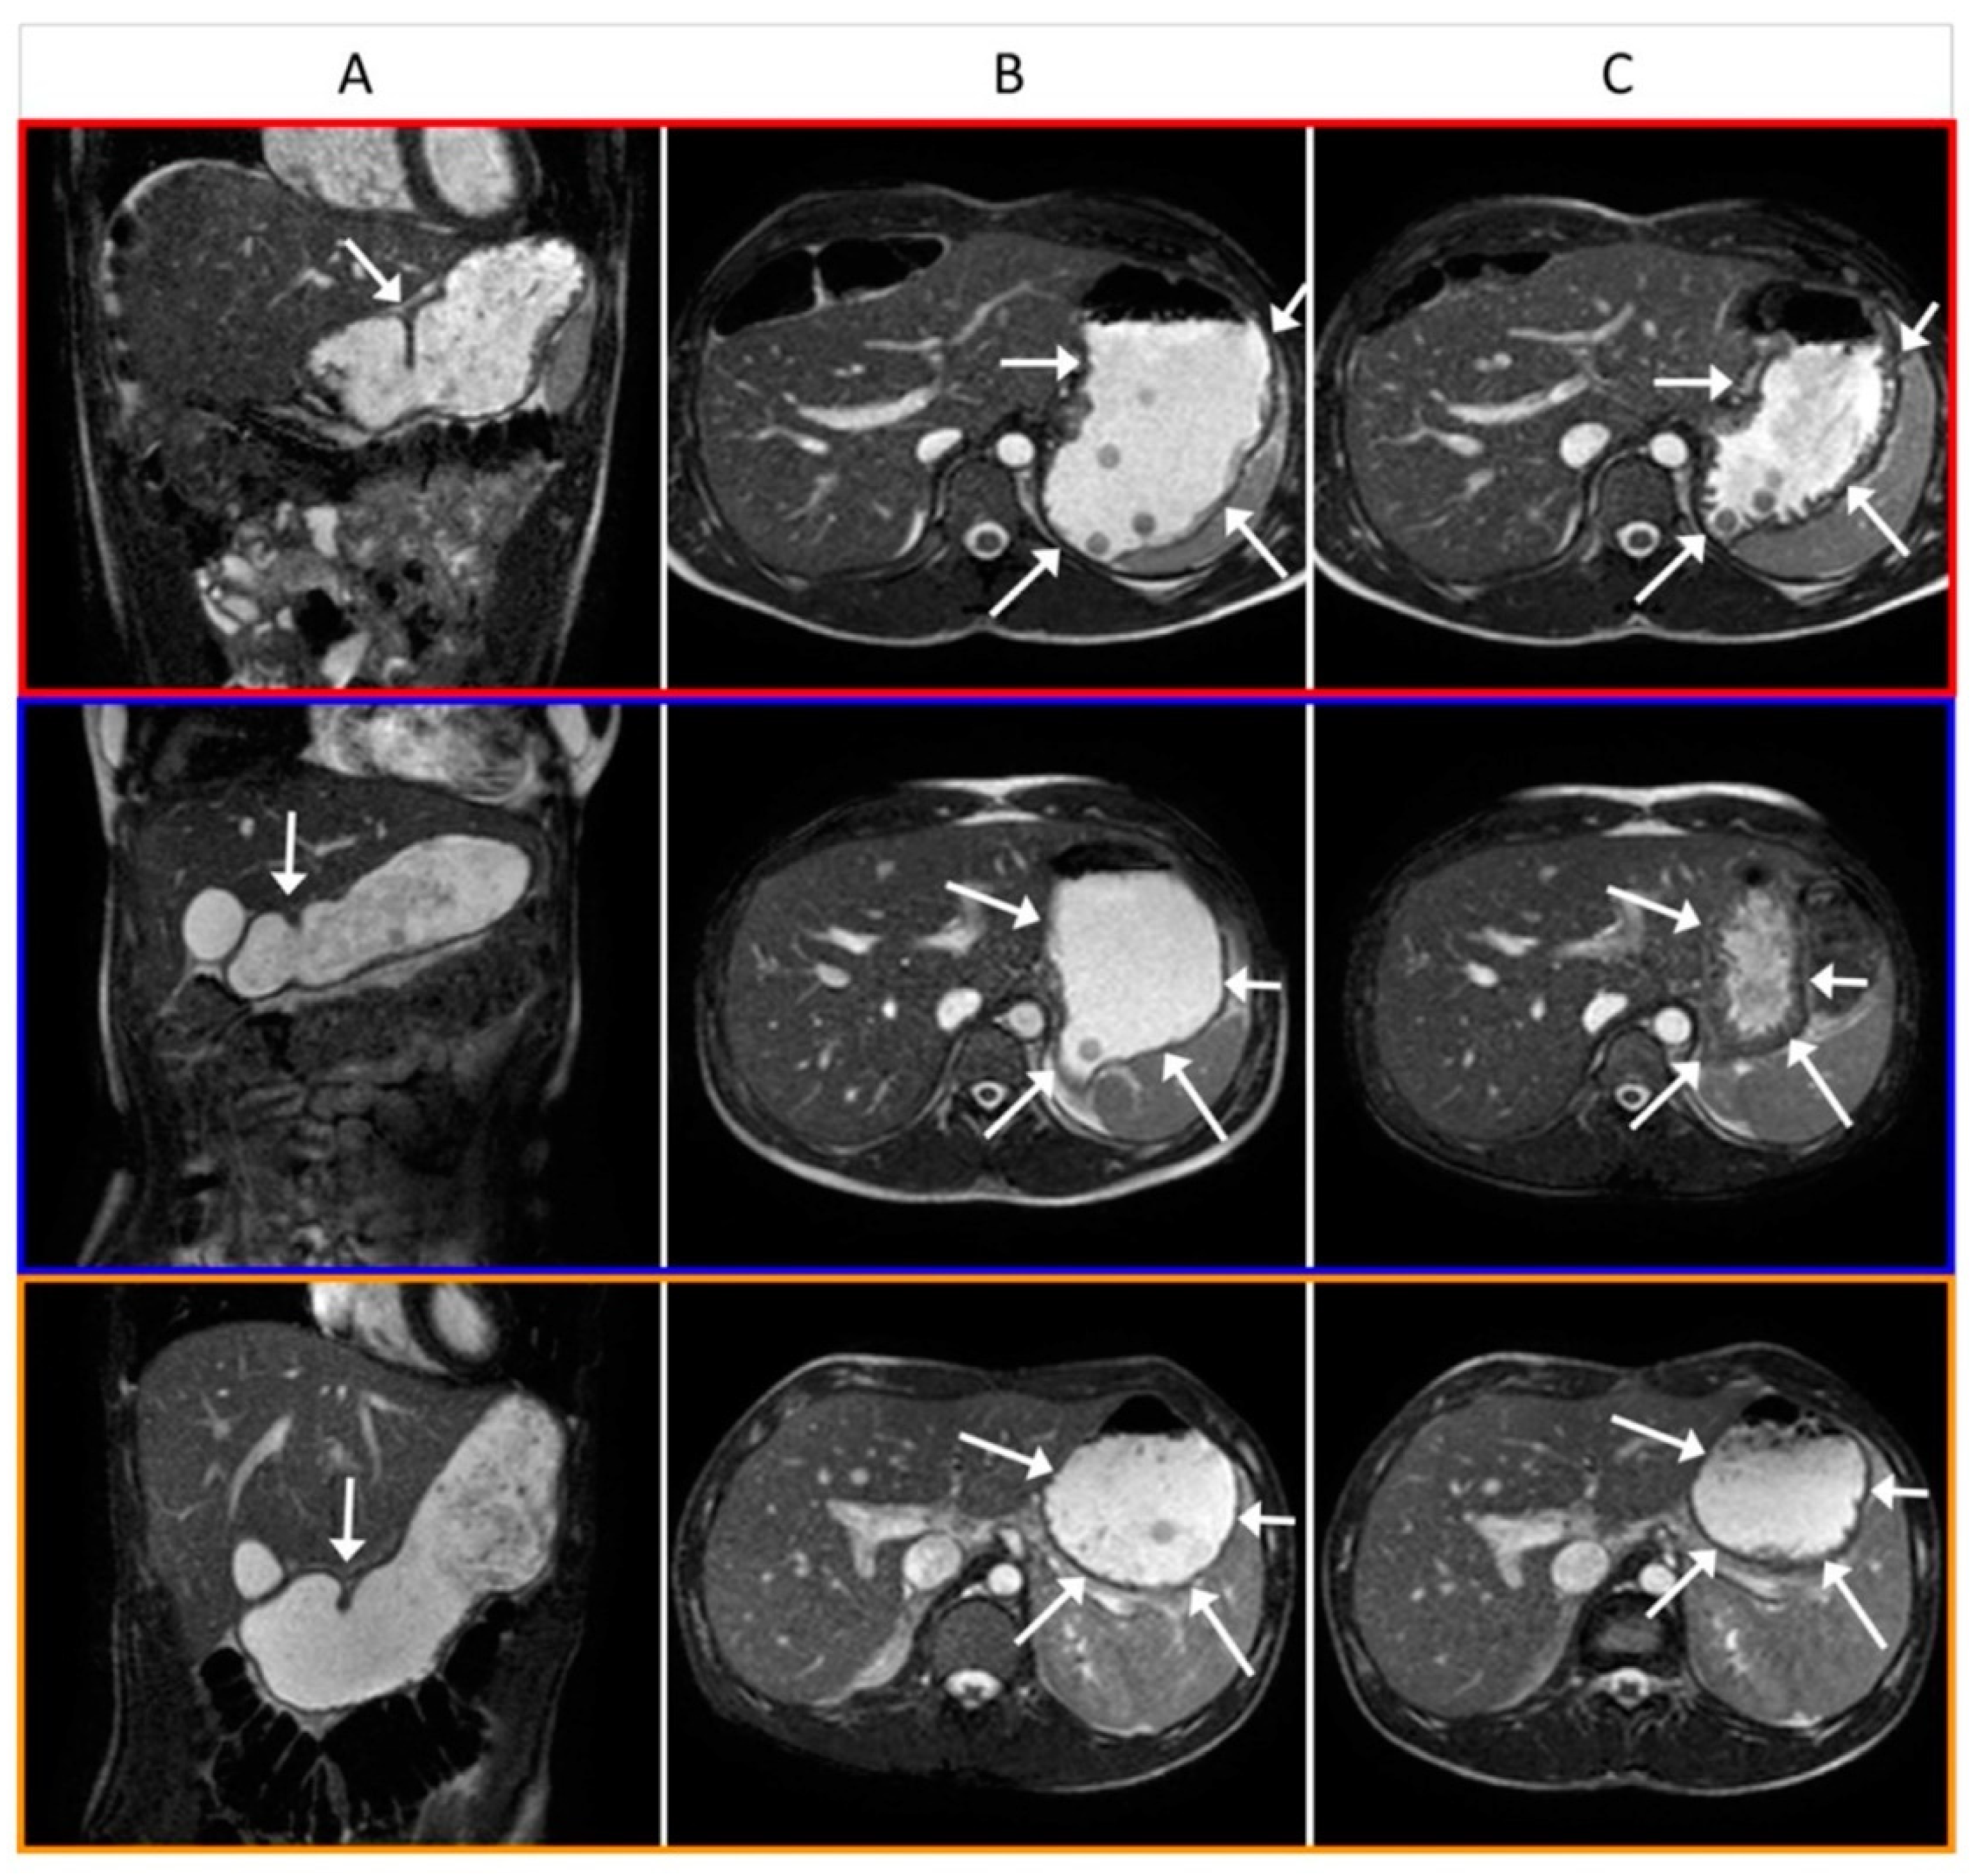

3.2. Gastric Magnetic Resonance Imaging

3.4. Image Analysis

4.4. Gastric Volume, Motility and Emptying